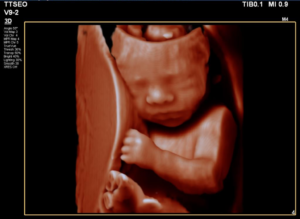

3D pretecho vanaf 26 weken

Bij deze echo is het natuurlijk heel leuk om met meedere mensen te komen. Lekker zitten en kijken naar hoe prachtig je kindje al ontwikkeld is! Als je baby er goed voor ligt, kun je heel mooi het gezicht in 3D en zelfs 4D zien! Je kunt al vaak zien dat je kindje aan het duimen is om lekker met zijn of haar teentjes aan het spelen is. Je krijgt alle beelden (inclusief filmpjes) mee op een USB-stick en ook wat plaatjes geprint mee. De kosten voor de echo zijn €75 en duurt 30 minuten. Je kunt zoveel pretecho’s plannen als je wil!